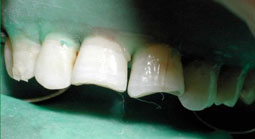

Une patiente âgée de 33 ans consulte au service des urgences, suite un traumatisme dentaire. A l’examen clinique, la 11 et 21 présentent des fractures coronaires horizontales non compliquées.

La prise en charge d’urgence consiste à réaliser une fermeture des tubuli dentinaires exposés au milieu buccal suite au traumatisme. A cet effet, des reconstitutions aux composite monochrome sont mises en place.

A une semaine, le contrôle de la vitalité pulpaire s’avère favorable ; il est positif sans signes de complication pulpaire. Les reconstitutions au composite sont rectifiées. Une fois leur forme jugée correcte par la patiente, ces reconstitutions serviront à la réalisation de la clé en silicone qui guidera la reconstitution finale des dents par technique de stratification (4) (Fig.7a).